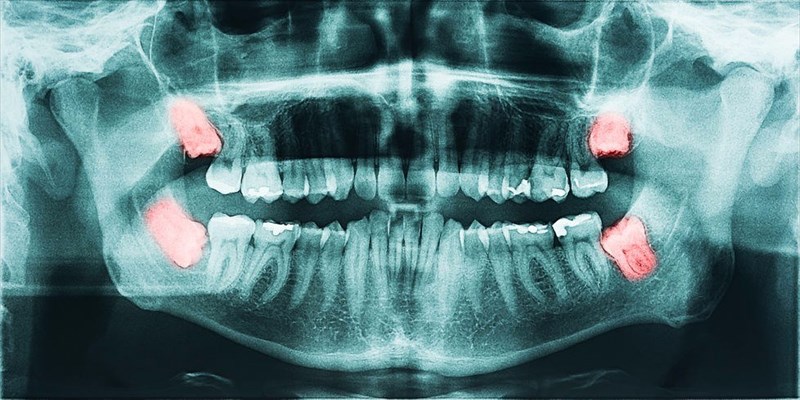

Wisdom Teeth Removal During Pregnancy. Can you get wisdom teeth removed when you're pregnant? The teeth can be removed as safely as possible before, during, or after the pregnancy, according to the needs of the expectant mother and the unborn child.

Wait till after pregnancy to get the extraction done. Risks of wisdom teeth removal during pregnancy. The optimum time for wisdom tooth extraction during. There are both risks and benefits to having wisdom teeth removed. As you may know, specialists typically administer anesthesia when removing wisdom teeth. Risks of removing wisdom teeth while pregnant. Vomiting and acid reflux commonly experienced with morning sickness can also erode the enamel, thus causing decay. These include thrush, gum inflammation, and tooth pain. Dental emergency professionals highly recommend for pregnant women to undergo routine cleanings, especially because of the inflammation that commonly occurs in the mouth during.

Wisdom tooth extractions are technically a type of oral. These include thrush, gum inflammation, and tooth pain. All you need to know about wisdom tooth extraction during pregnancy from parentinghealthybabies.com. There are both risks and benefits to having wisdom teeth removed. This includes wisdom teeth extraction, though most dentists prefer to. Another thing is serious indications: Severe decay can necessitate wisdom teeth removal. The optimum time for wisdom tooth extraction during. Wisdom tooth extraction is a common dental procedure, but it is one that pregnant women may have questions about it.

What is the safest time to schedule wisdom teeth removal?. However, if you aren’t experiencing severe symptoms, the tooth extraction doesn’t need to happen during. The cause of teeth pain during pregnancy one of the most common causes of this pain is the fact that women’s hormone levels change a lot during pregnancy. Has anyone had all four wisdom teeth removed during pregnancy? Risks of wisdom teeth removal during pregnancy. Visit your dentist and have. Generally, yes — in fact, most dental procedures are safe during pregnancy, except for maybe whitening. Hence, if you are avoiding your wisdom tooth extraction due to monetary reasons during pregnancy, be assured that today cheap wisdom teeth removal is a reality. Risks of removing wisdom teeth while pregnant.